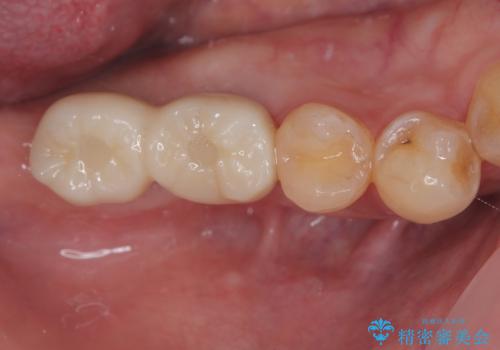

虫歯の範囲が大きく、部分的な詰め物では対応が難しいため、オールセラミッククラウンにて補綴することとしました。

定期的に歯科医院を受診し、早期発見・早期治療をすることで、歯の神経を残す治療が可能になります。